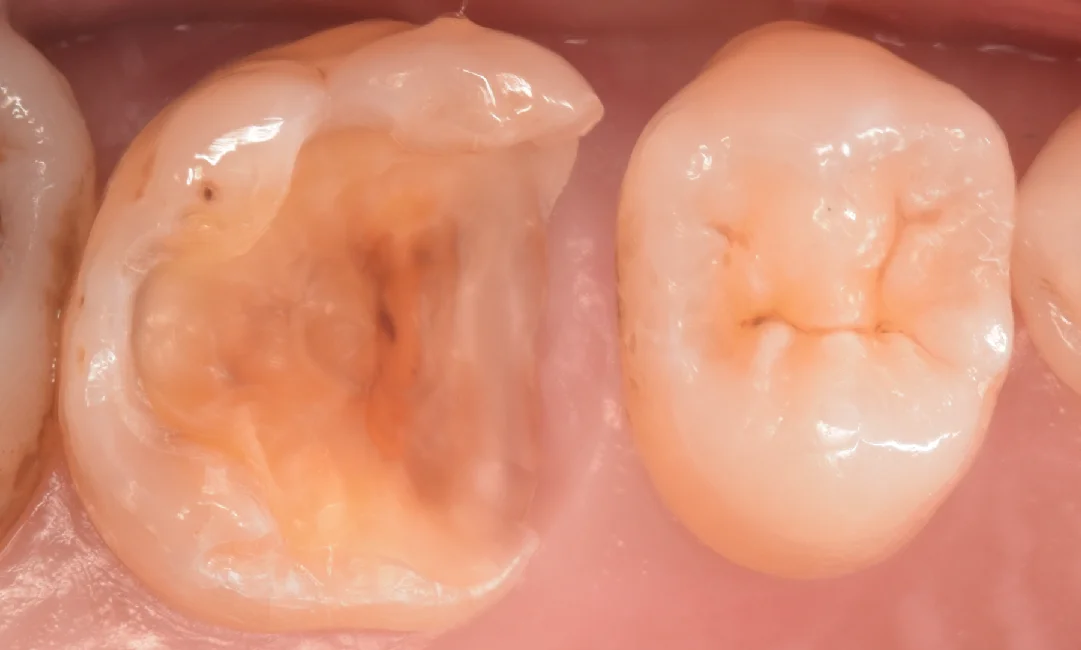

金属と古い詰め物を除去して虫歯を見やすくしたのがこちらになります。

全体的に黒くなっているのがわかるかと思います。

また、隣の歯との間については歯茎の下まで黒くなっているのがわかります。

虫歯を取り切ったのがこちらになります。

神経が相当ギリギリでしたね・・・

また歯茎からはおおよそ1.5mmほど深くまで虫歯になっていました。

歯茎を傷つけずに除去できたため、1.5mm深くとも歯茎からの出血はありません。